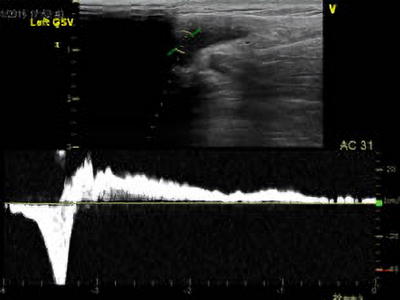

下肢静脈瘤では血液が正しい方向に流れず逆流を起こしている状態ですので、この検査では血液の逆流の有無を調べます。 ボコボコとこぶになるタイプの静脈瘤が起こりやすい伏在静脈を検査しますので、足の付け根から足の内側を通り内くるぶしの方へかけてと、膝裏からふくらはぎの後ろ側を通り、かかとにかけて診ます。